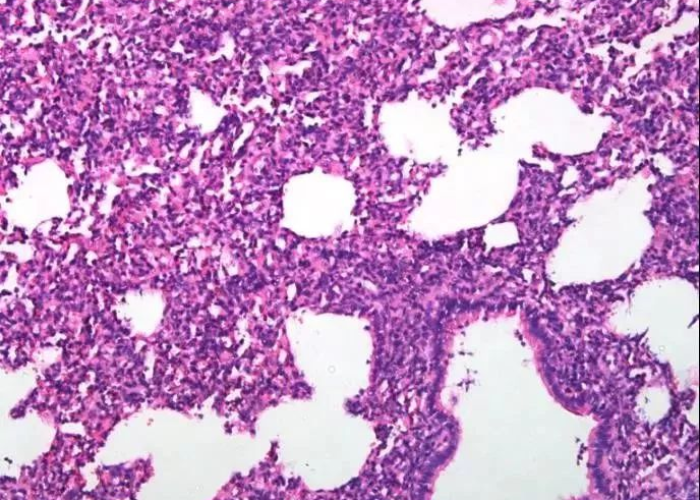

特征性肺部听诊音

约50%的早期患者在肺部听诊时可闻及Velcro啰音( Velcro crackles),这种声音类似于撕开尼龙扣时的细微爆裂音,这是肺泡壁增厚和间质水肿的典型表现,但需要专业医生通过听诊器才能识别。